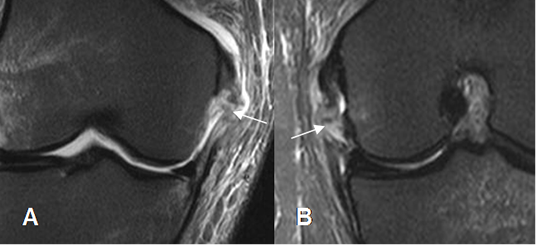

En las lesiones crónicas, se aprecia engrosamiento por fibrosis y pérdida de la grasa entre los fascículos. (3). (Fig 121).

Fig 121. Fibrosis del LCM.

A: RM coronal en T1 y B: RM coronal en STIR. El LCM se aprecia engrosado, aunque conserva su señal, por fibrosis residual.